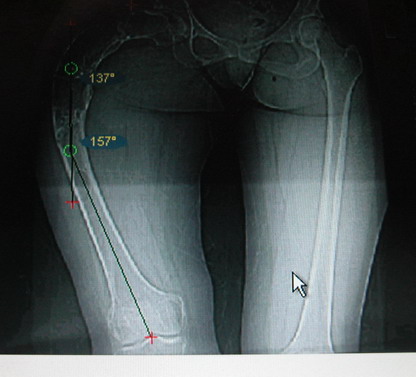

Женщина 28 лет, Больна с 12 летнего возраста, Когда после адекватной травмы получила перелом бедра. На рентгенограммах выявлено какое-то (рентгенограмм и документов нет) изменение бедренной кости, была оперирована, имеется гистологическое заключение - фиброзная дисплазия.дСформировалась деформация бедра. На сегодня - Укорочение 7см. Грубая деформация бедра по типу "пастушьей палки", последний патологический перелом в январе 2004г., консолидировавшийся при консервативном лечении. Имеются грубые изменения и в надвертлужном массиве.-- С уважением, Leonid

Возможна аппаратная коррекция оси с формированием клиновидного регенерата, которая решила бы и проблему укорочения (что, впрочем, нужно уточнить по схеме, сделанной по рентгенограмме с хорошим захватом смежных суставов - схемка по присланному снимку в приложении). По окончании коррекции - блокируемый стержень, который и сократит время пребывания в аппарате, и вообще возврата к нормальной жизни, а также будет мерой профилактики патологических переломов.

Собственно сустав не беспокоит, объем движений полный. По скиаграммам получается, что достаточно одной остеотомии на вершине деформации, чтобы восстановить длину и вывести коленный сустав в нужное положение.

Т.к. укорочение 7 см, то начинать будем с соеотомии и коррекции аппаратом. Спасибо

Моё мнение, что двойная остеотомия бедра с аппаратом Илизарова + Гексаподный механизм, или Тэйлора, В данной ситуации является методом выбора. Я очень извеняюсь за качество прилагаемых снимков, в которых я постарался отразить разницу междe одной и двумя остеотомиями бедра.